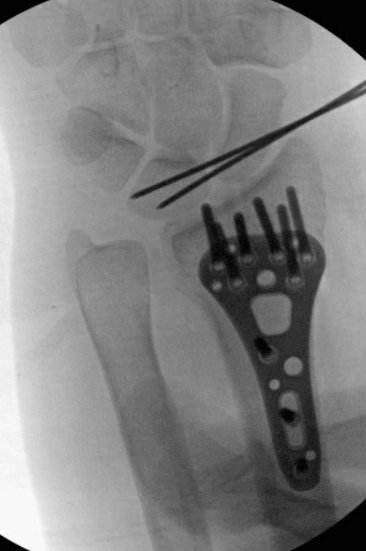

Given the dominant-sided injury, radial and intemediate column injury, joint diastasis, possible SL injury, patient's age, we discussed surgery.

We decided that there was no better way to identify the SL injury other than with our eyeballs. So, scope/fix bone/address ligament.

Of course, the scope tower saved whichever images it felt like. Membranous SL tear, no drive through, no shuck.

Scope assisted reduction of the articular surface was pretty cool, but radiographs honestly showed the same story

Ordinarily, I’d change that long/distal screw out, but since I was scoping the joint and didn’t see penetration, I felt ok leaving it

Debrided and pinned the SL